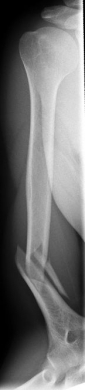

Oberarmschaftbruch1Oberarmschaftbruch2

Picture: Here you can see a completely shifted upper arm fracture with a strong bend of the axis. First the operative treatment was performed by repositioning the bone and internal splinting of the fracture with a medullary nail.